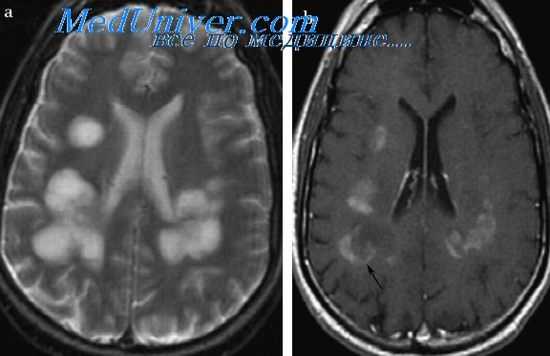

В гемограмме определяют умеренно выраженный нейтрофильный лейкоцитоз, в цереброспинальной жидкости выявляют невысокий лимфоцитарныи плеоцитоз до 50-100 клеток в 1 мкл и увеличение содержания белка (гиперпротеинорахия) При КТ и МРТ головного мозга выявляют очаги поражения в базальных ганглиях, таламусе и стволовых отделах

Радиографические методы исследования (КТ и МРТ) выявляют значительные очаги поражения в области базальных ганглиев, таламуса и ствола мозга.